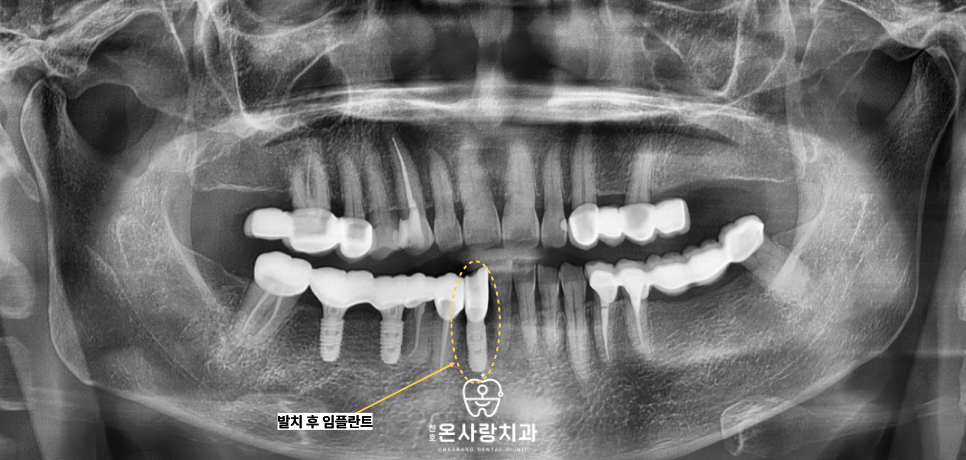

천호역임플란트를 식립하여

단독적인 지지력을 확보하였습니다.

또한 기존에 치아가 비어 있던 자리에는

인공치아인 천호역임플란트를 식립함으로써

브릿지에만 의존하던 구조에서 벗어나

각 치아가 독립적으로 씹는 힘을

견딜 수 있도록 재구성하였습니다.